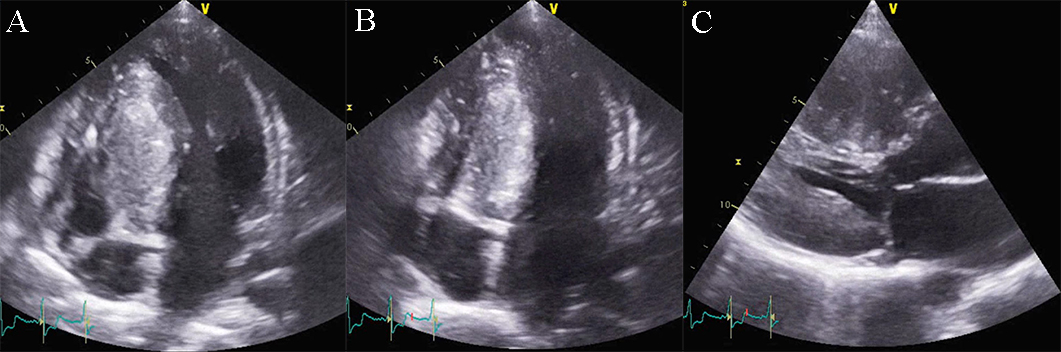

Doppler echocardiography and tissue Doppler imaging show diastolic dysfunction, frequently with a restrictive pattern. Different aspects of the diastolic function can be revealed, but usually more than grade 2 diastolic dysfunction, with increased filling pressures: an elevated peak mitral inflow velocity (high velocity of E wave), rapid early mitral inflow deceleration (low deceleration time). E/A ratio greater than 0.8, deceleration time of E wave lower than 200 milliseconds, and frequently lower than 160 milliseconds, E/e’ ratio with a value above 9, are features found in the echocardiographic examination of RCM (see Fig. 10 and Appendix Video 5) [1, 4].

Fig. 10.Echocardiographic aspect of RCM. (A) Apical 4c view of an

elderly patient with idiopathic restrictive cardiomyopathy, severe biatrial

enlargement (left atrium